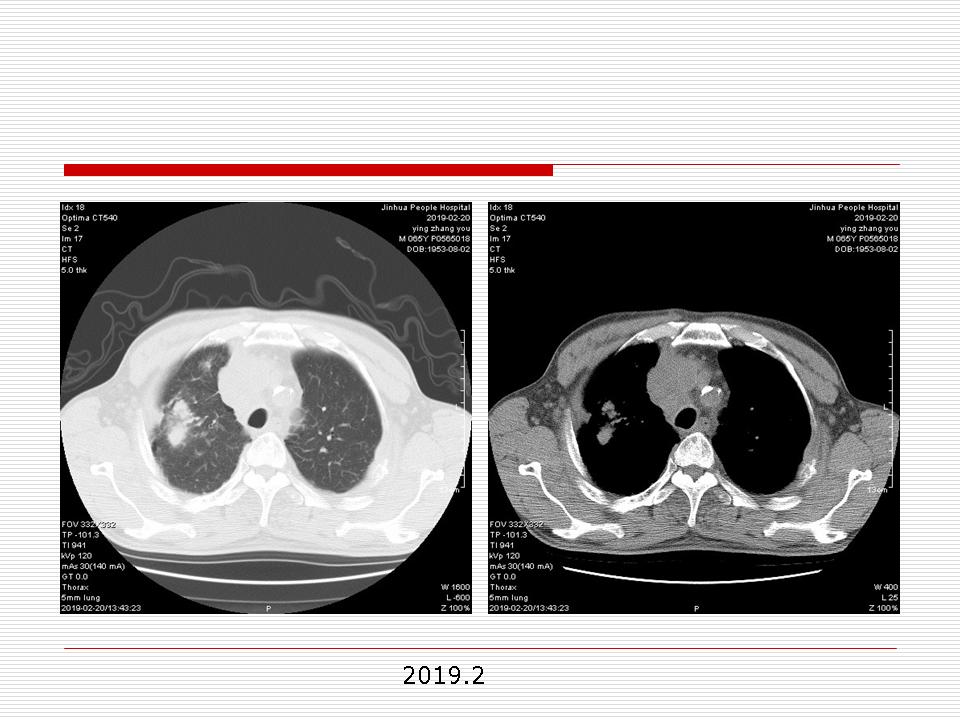

肺部阴影永恒且最重需要鉴别的是:到底是炎症还是肿瘤?但临床的病例中的影像表现难以界定或有些肿瘤特征,同时又有些炎症特点是非常常见的情况。作为临床医生我们怎么去总结分析,并找到之所以是炎症或之所以是肿瘤的细微差别或特点非常重要,也非常有用。2019.12.7浙江省2019年胸心外科学学术年会在宁波召开时,我的临床病例分析与经验总结<那些像肺癌的炎症与像炎症的肺癌>获得在大会交流的机会,以下为该PPT的内容,与你分享,希望对同道有益,有借鉴与启迪。若有探讨与进一不完善的建议,欢迎文末留言讨论: